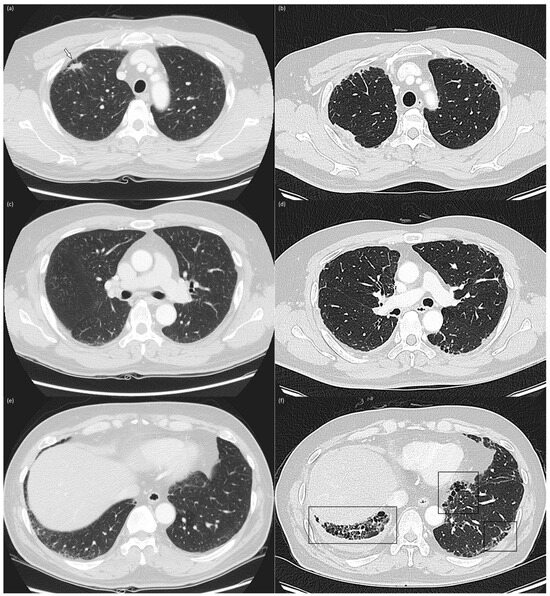

The baseline and corresponding follow-up CT scans were simultaneously reviewed to determine progression [13]. Progression was defined as an increase in the lung area or a new appearance of an interstitial abnormality (Figure 2). Progression was assessed only in patients with an ILA score of 2 on the follow-up CT. In the case of a discrepancy between the two raters, the final decision was made by consensus.

Figure 2.

Baseline and 4-year follow-up chest computed tomography images Baseline (a,c,e) and 4-year follow-up (b,d,f) chest CT images in the upper (a,b), middle (c,d), and lower (e,f) lung zones of a 56-year-old, male current smoker with a 60 pack-year smoking history. The baseline CT reveals subpleural reticulation and mild traction bronchiolectasis in both lungs, suggesting the presence of fibrotic ILAs. A 1.5 cm-sized nodule (arrow) was identified in the right upper lobe and confirmed as adenocarcinoma (a). The patient underwent right upper lobe lobectomy and adjuvant chemotherapy with cisplatin and paclitaxel. The 4-year follow-up CT reveals increased subpleural reticulation, traction bronchiectasis, and honeycombing (box), predominantly in lower lung zones, indicating ILA progression.